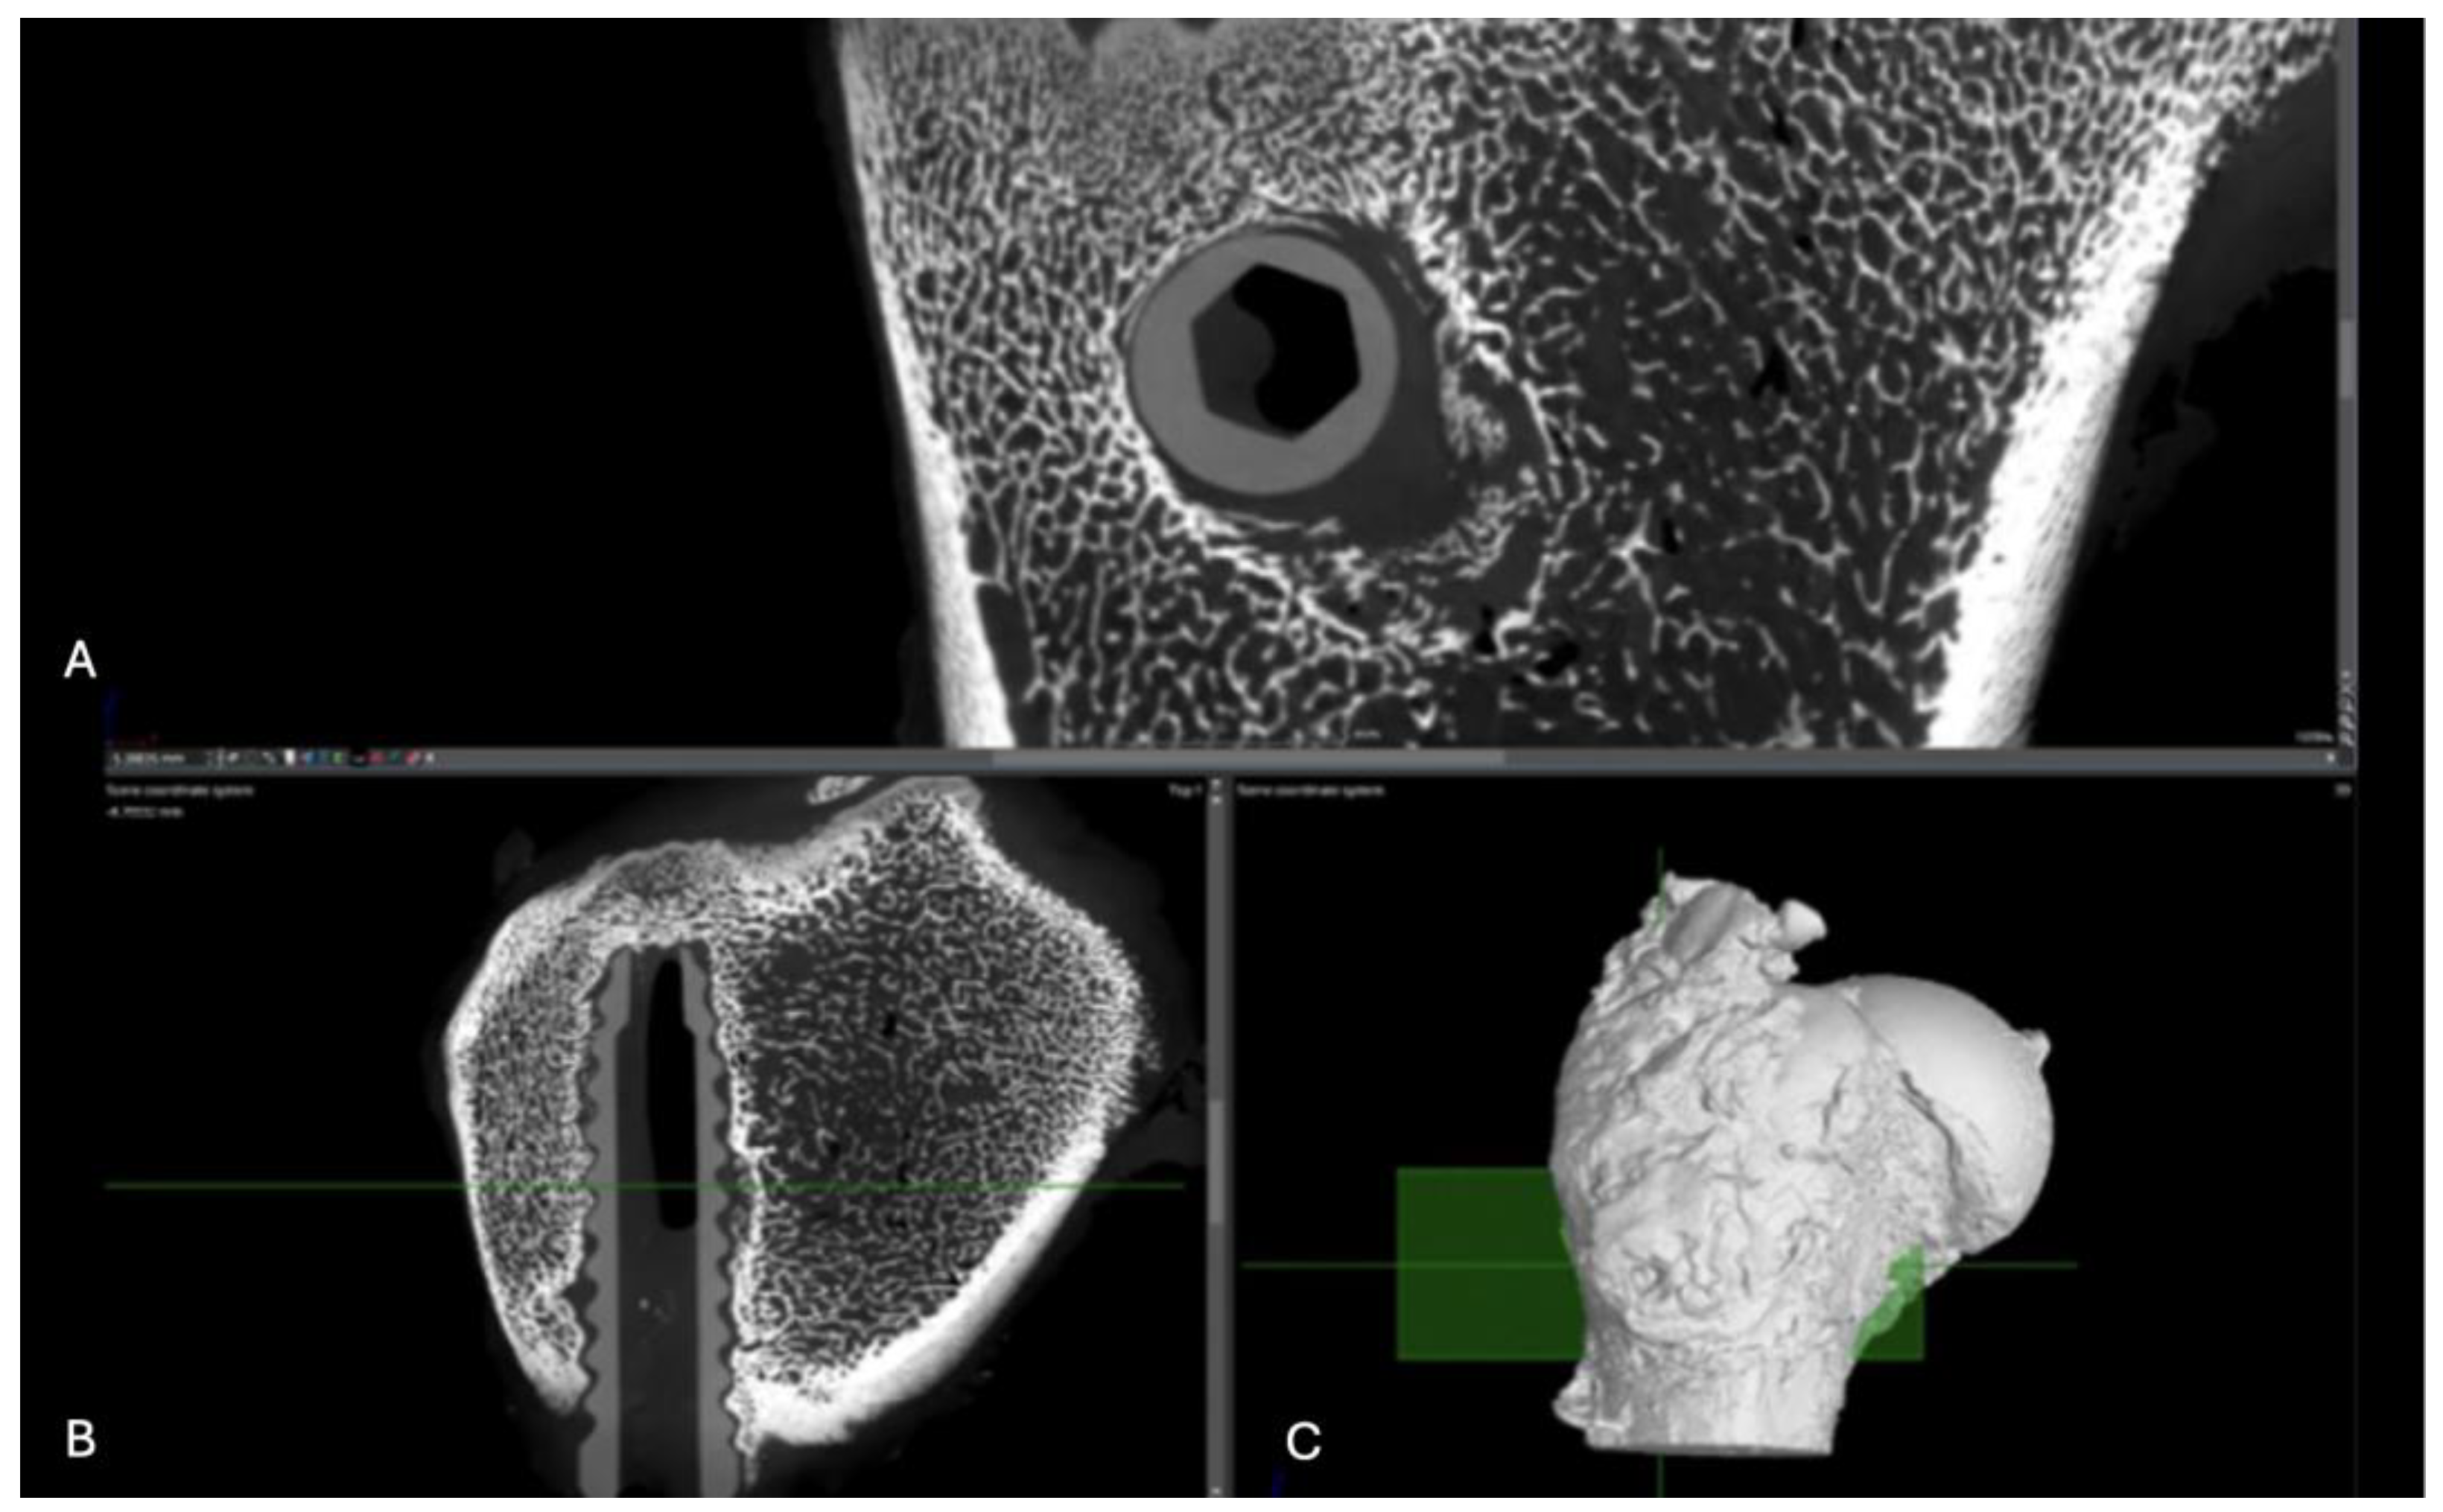

Figure 18. Computed tomography study of the right femur sample, three-month post-surgery, with PLA material. . (A) sagittal reconstruction, (B) axial and (C) 3D imaging.

PLA: The right femur of a surgically treated pig was examined after a three-month postoperative period using axial cuts, sagittal reconstruction, and 3D visualization. In the transverse section, a significant increase in bone trabeculation is observed, obstructing approximately 90% of the tunnel created for the insertion of the screw. In the sagittal view, an increase in circumferential hyperdensity around the screw is noted, indicating enhanced bone growth that contributes to a more stable fixation. (Figure 18)

Figure 21. Computed tomography study of the left femur sample, fourth-month post-surgery, with PLA material. (A) axial, (B) sagittal reconstruction and(C) 3D imaging.

PLA: Partial view of the left femur in a pig at a four-month postoperative follow-up, assessed through axial slices, sagittal reconstruction, and 3D visualization. Across all images, hyperdense areas identified, indicating bone growth into the interior of the PLA screw. Additionally, there is a partial increase in circumferential density toward the distal third of the screw, suggesting proper osseointegration and bone formation. (Figure 21)